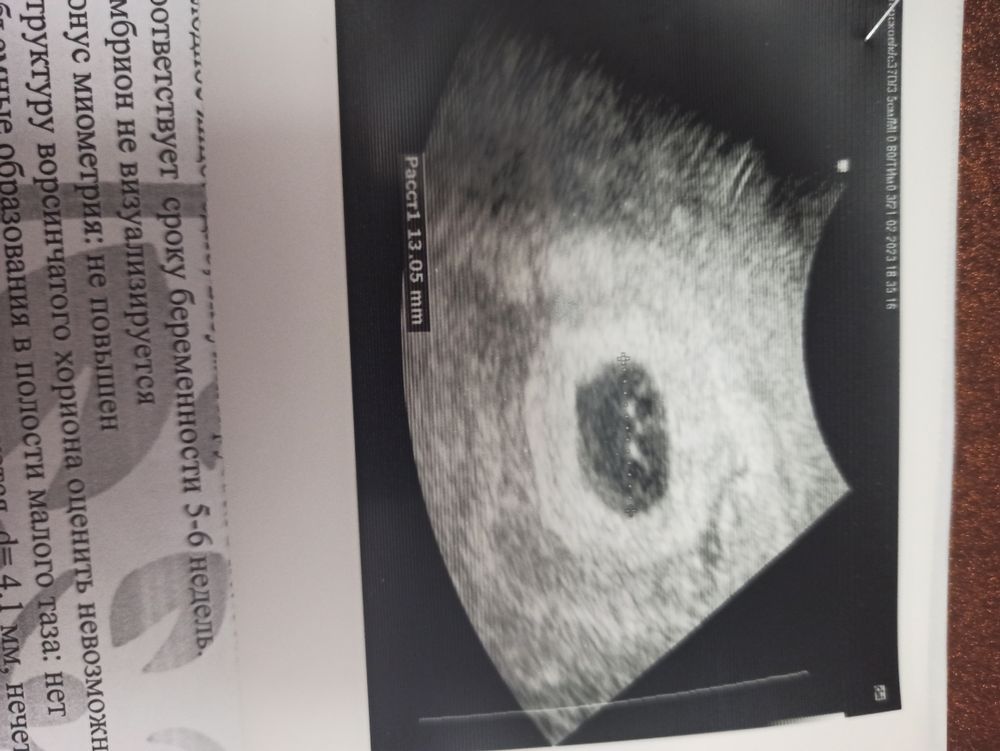

Вобщем, не выдержала и пошла платно на УЗИ ( начало истории в предыдущей записи) . Пошла туда же, где делала первое узи. С собой заключение не взяла, а по сроку месячных узистка сначала погрустела. Но потом нашла первое заключение и сказала что никаких чисток, динамика прироста хорошая! Просто вероятнее всего беременность наступила на 2 недели позже, чем считать по месячным.

А ещё, она нашла второй плодный мешочек!! Сказала видно не очень хорошо, но есть вероятность!

Евгения , эмбриона нет, срок 5-6 недель ставят, повторно на УЗИ через 2 недели

Ксения Рунова, размер если плодного яйца 13 мм, то еще есть шанс конечно, что появится. Дай бог🙏🏼